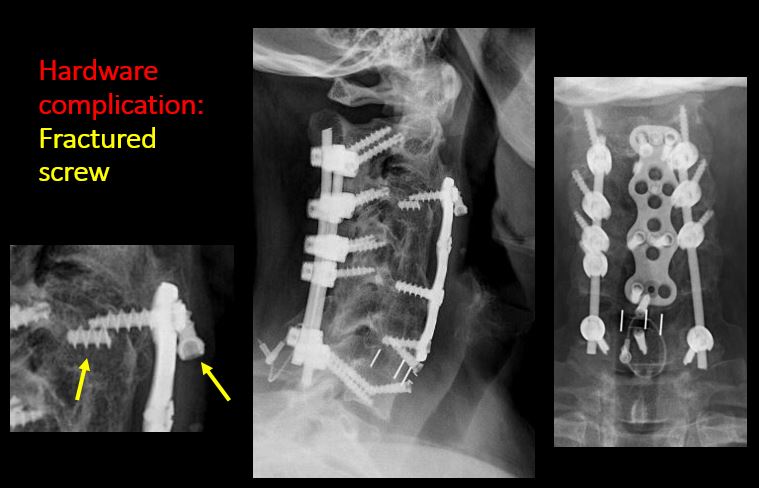

There are post surgical changes of the bones or soft tissues of the lower head, neck, or upper thorax.

The included maxillofacial region, thoracic spine, ribs, or other bones of the upper thorax are abnormal.